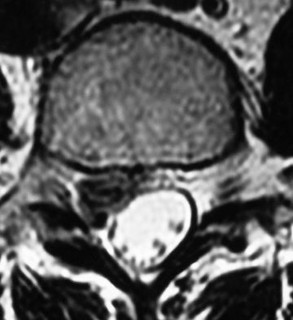

A 65-year-old male presents with progressive clumsiness in his hands, difficulty buttoning his shirt, and a wide-based gait. Physical exam reveals a positive Hoffmann's sign bilaterally.

MRI of the cervical spine demonstrates multilevel degenerative spondylosis with cord compression. Which of the following MRI findings is considered the strongest independent predictor of a poor neurologic recovery following surgical decompression?

Explanation